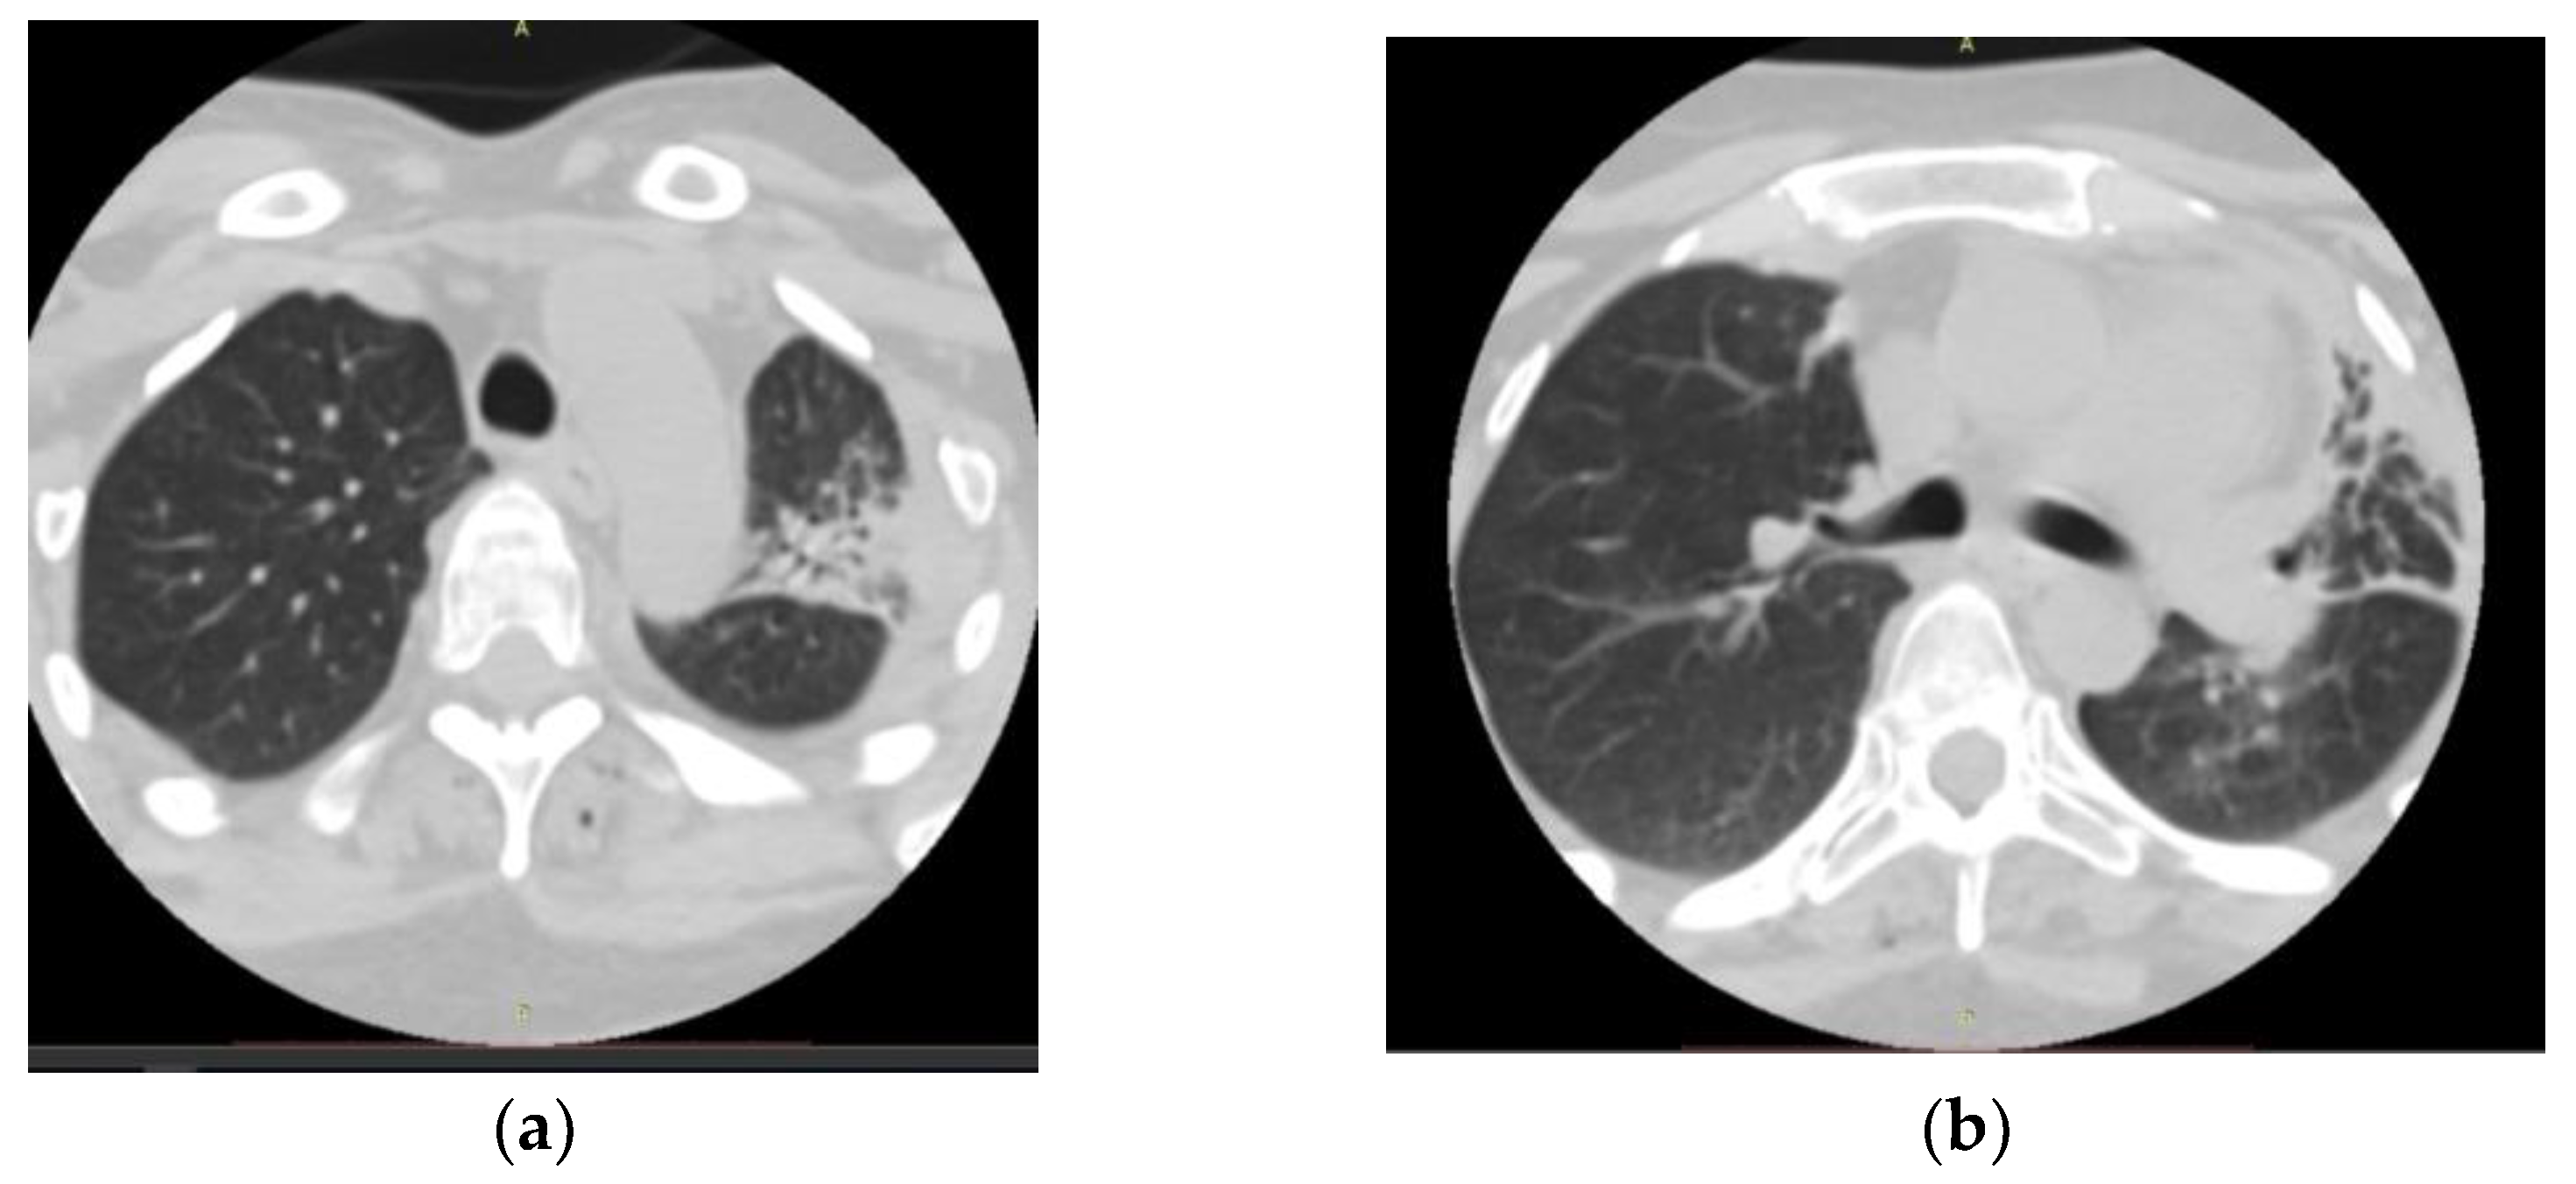

- Three-month duration of pulmonary symptoms;

- Radiological evidence of chronic pulmonary lesion;

- Mycological demonstration of Aspergillus fumigates hyphae by microscopy from spu-tum, microscopy and culture from bronchial aspirate, and histopathological evi-dence of the presence of Aspergillus fumigates hyphae with dichotomous branching in the spinal cord biopsy;